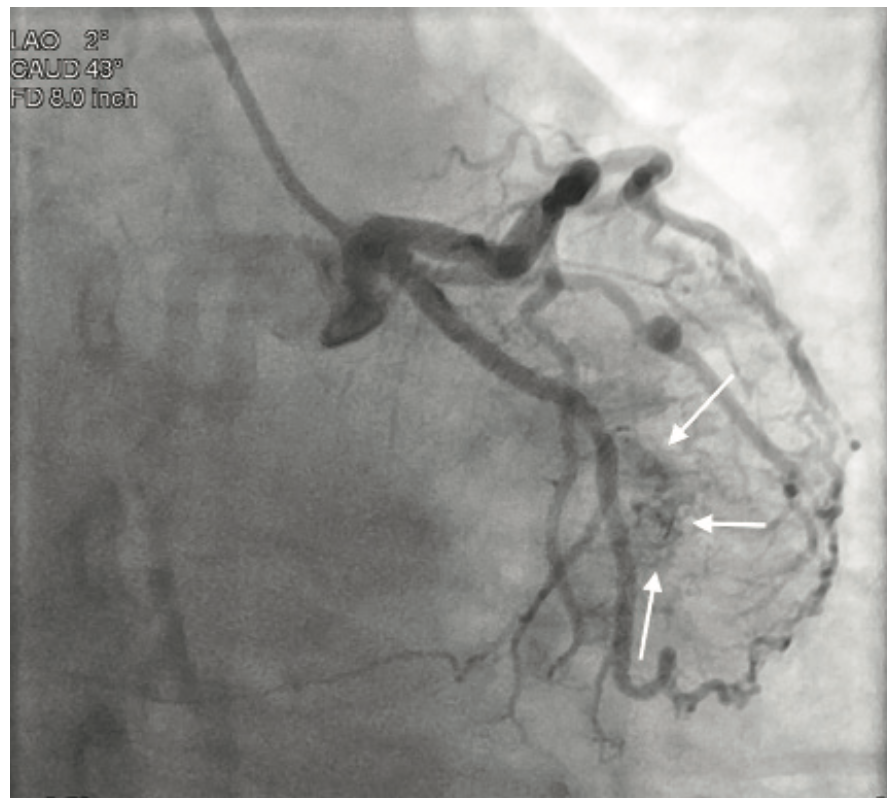

Video 2. Visualization of the apical and anterior walls of the ventricle.

Coronary angiography revealed no significant coronary artery disease, with only a minor lesion in the proximal right coronary artery. Left ventriculography was performed using a power injector. The patient had an approximate ejection fraction of 60% and there was no angiographic evidence of regurgitation. Following coronary angiography, the patient underwent an echocardiogram to further investigate the systolic murmur. No significant findings were discovered; however, a bicuspid aortic valve was noted, a congenital anomaly occurring in 1-2% of patients.1 Although the coronary arteries showed no significant disease, there was significant capillary blushing during injections of the left coronaries. A closer review of the images showed the blushing originating from a diagonal branch of the left anterior descending artery with a direct connection to the interior of the left ventricle, effectively providing a simultaneous coronary angiogram and ventriculogram.

Thebesian veins are generally found incidentally during coronary angiography2 and are the remnant of nutrient supply pathways in the embryonic heart3. In this case, the vessels provide a direct connection from the epicardial coronary arteries into the left ventricle. Although Thebesian veins are a rare angiographic find and the clinical effects are not entirely clear, they can make for very dramatic and interesting angiography.